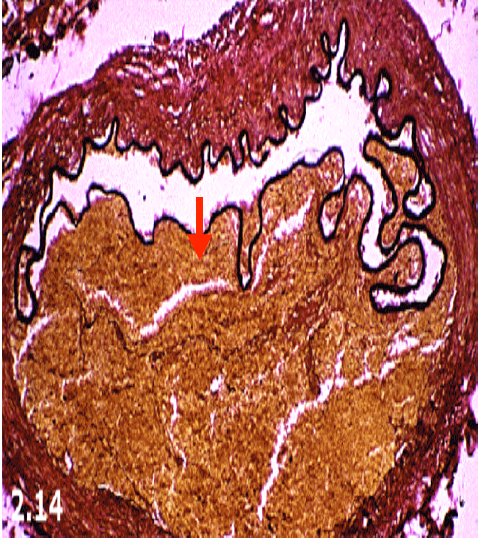

What are the small cells on the very outer layer? They form the arachnoid membrane.

What do they stain with?

Meningothelial cells

Stains positive for epthelial membrane antigen (EMA)